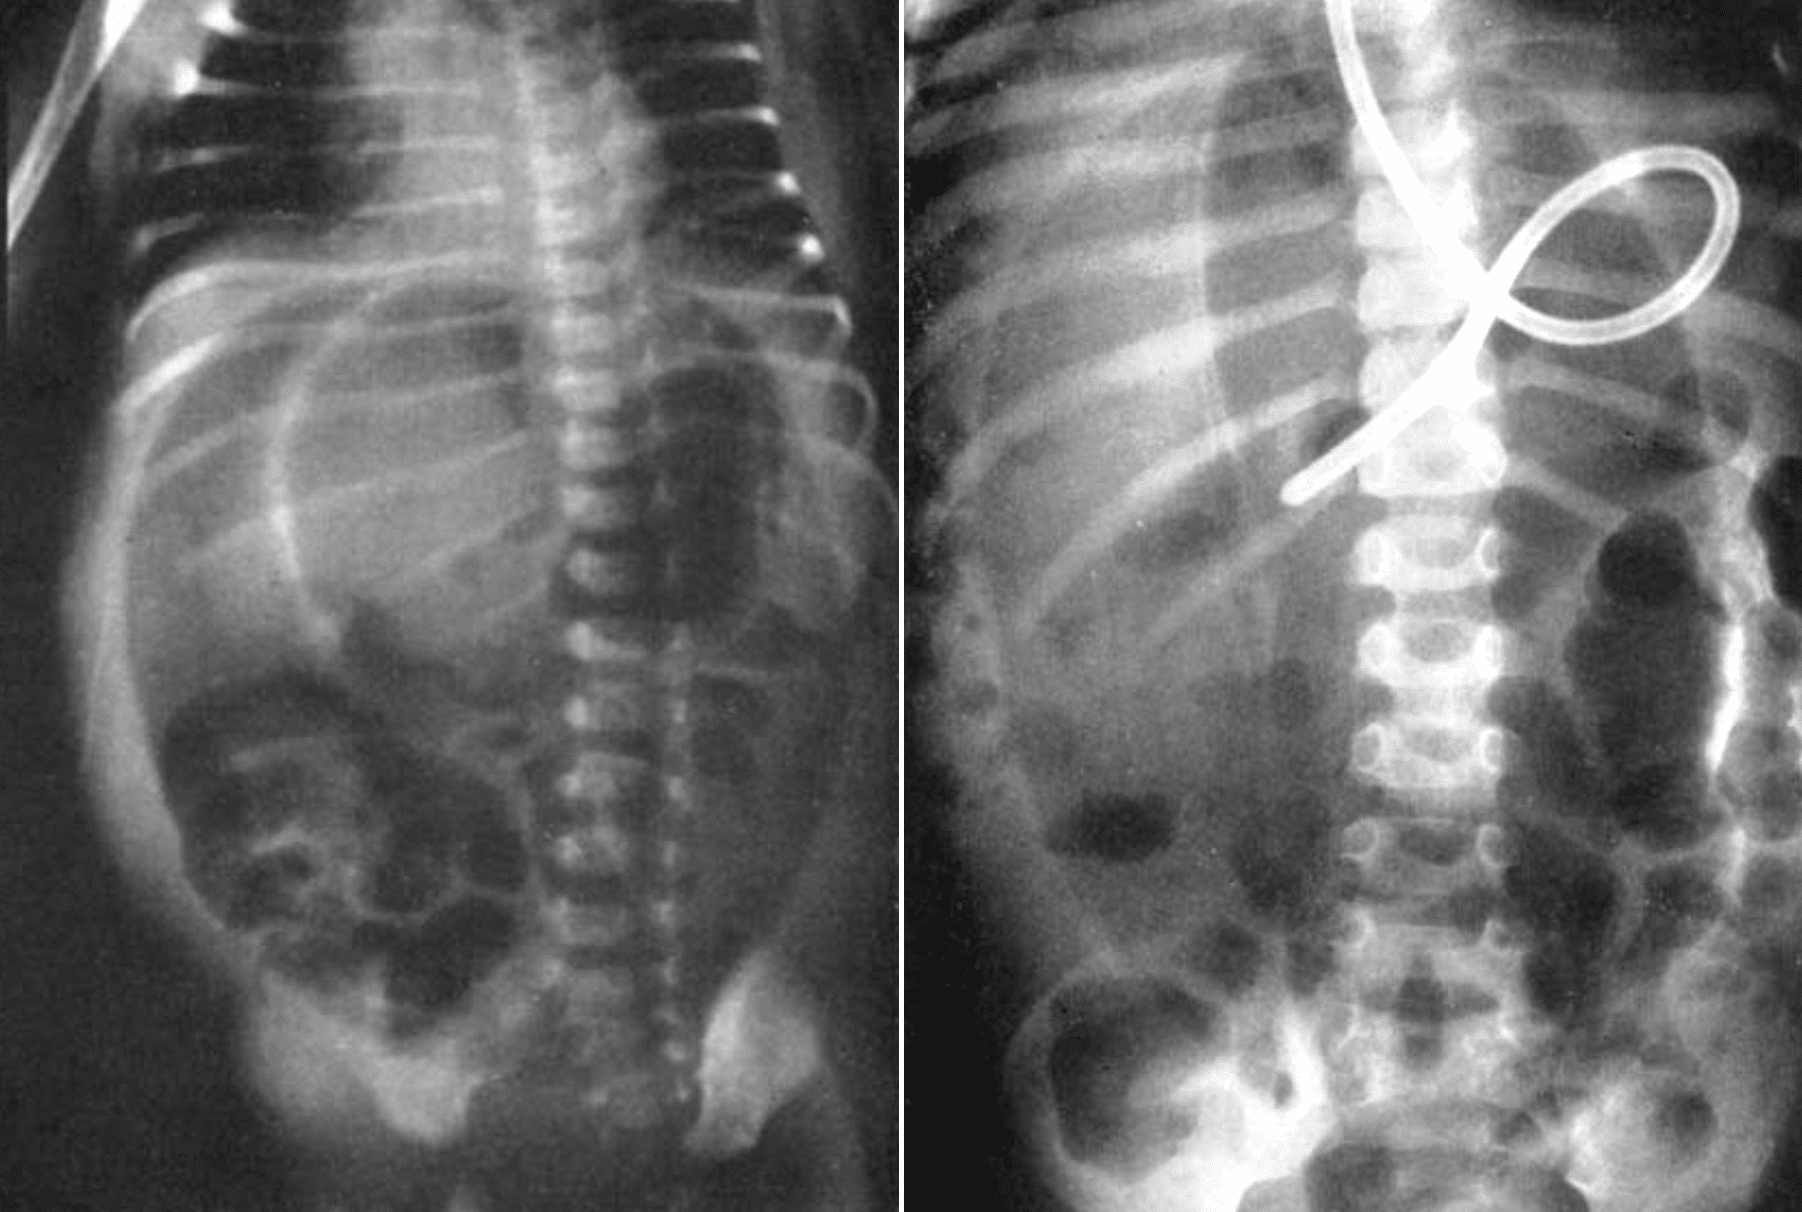

1960 – Roscoe E. Miller (1918-1984) of the Indiana University School of Medicine described the “air dome” sign in a series of infants with gastric, duodenal, or colonic perforation. This was based on a large review of supine radiographs from patients too ill for erect imaging.

Figure 2: Supine radiograph in a 4-year-old showing similar air dome, with confirmed duodenal perforation at autopsy. Miller 1960

Miller’s sign emphasised the early and specific recognition of free air in neonates using only supine films, significantly aiding diagnosis when other signs were absent or patients were non-ambulatory.

Confirmatory upright films may be taken, but it is unnecessary if the “air dome” sign is seen on the supine view. The “football” or “air dome” sign is pathognomonic and leads to early diagnosis and surgical intervention…The characteristic oval line of the “air dome” divided by the streak of the falciform ligament is pathognomonic.

Miller, 1960